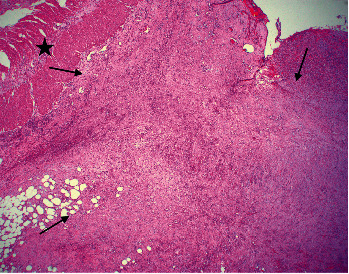

Inflammatory myofibroblastic tumor (IMT) is a rare mesenchymal tumors of unknown etiology composed of myofibroblastic cells admixed with inflammatory cells. Presented is a 72-year-old male hospitalized for severe abdominal pain and hematochezia with onset of associated symptoms of fever and sweats a few hours prior to abdominal pain. A computed tomography (CT) demonstrated left colonic thickening interpreted as partial obstruction, gross adhesions, and ischemia. At surgery, marked bowel ischemia from the distal transverse to proximal sigmoid colon was seen with extensive gross adhesions. Histopathology revealed a mesenteric mass chiefly composed of stellate-to-spindled myofibroblastic cells and fibrous adhesions, intermixed with lymphocytes, histiocytes, and plasma cells. The tumor was positive for desmin, smooth muscle actin, and keratin; tumor staging, grade, and postsurgical follow-up were not completed as the patient expired postoperatively. Illustrated is a rare pathologic mimic of ischemic colitis with fibrous adhesions, IMT. Thus, it should not be assumed that fibrous adhesions are always the etiology of obstruction when "adhesions" between sections of bowel are noted radiologically or surgically.

Abstract Image